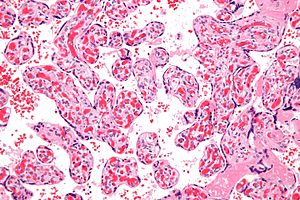

Chorangiosis. H&E stain.

Microscopic

• Increased blood vessels in the terminal villi.

• Altshuler criteria: "a minimum of 10 villi, each with 10 or more vascular channels, in 3 or more random, non-infarcted placental areas when using a ×10 ocular."[6][7][8]

• Villi tend to be larger and have centrally placed blood vessels.[9]

• Normal villi have up to five vascular channels.[7]